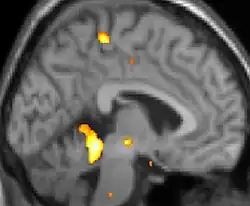

Tomografia PET mostrando áreas ativadas na dor.

As reais causas da cefaleia em salvas (CES) ainda são desconhecidas, mas, de acordo com alguns estudos, os padrões das crises, as influências pelo horário do dia e as estações sugerem que o relógio biológico do corpo está envolvido. Nos seres humanos, o relógio biológico está situado no hipotálamo. Durante um ataque, o hipotálamo libera substâncias químicas que podem estimular as células nervosas no cérebro, causando dor e outros sintomas. A hiperatividade nervosa também pode causar um alargamento (vasodilatação) das artérias no lado afetado do cérebro. Uma teoria é que as dores são causadas por um alargamento dos vasos sanguíneos, que pressionam sobre os tecidos nervosos próximos, causando dor.[5] Exames de ressonância magnética sugerem dilatação da artéria oftálmica durante uma crise de cefaleia, enquanto a tomografia por emissão de pósitrons (PET) revela atividade dentro do seio cavernoso. Em alguns casos, existem fatores genéticos também, pois é mais comum entre familiares.[6]